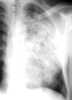

Primary tuberculosis

Tuberculosis (TB) is an infectious disease usually caused by Mycobacterium tuberculosis (MTB) bacteria. Tuberculosis generally affects the lungs, but can also affect other parts of the body. [Source: Wikipedia ]